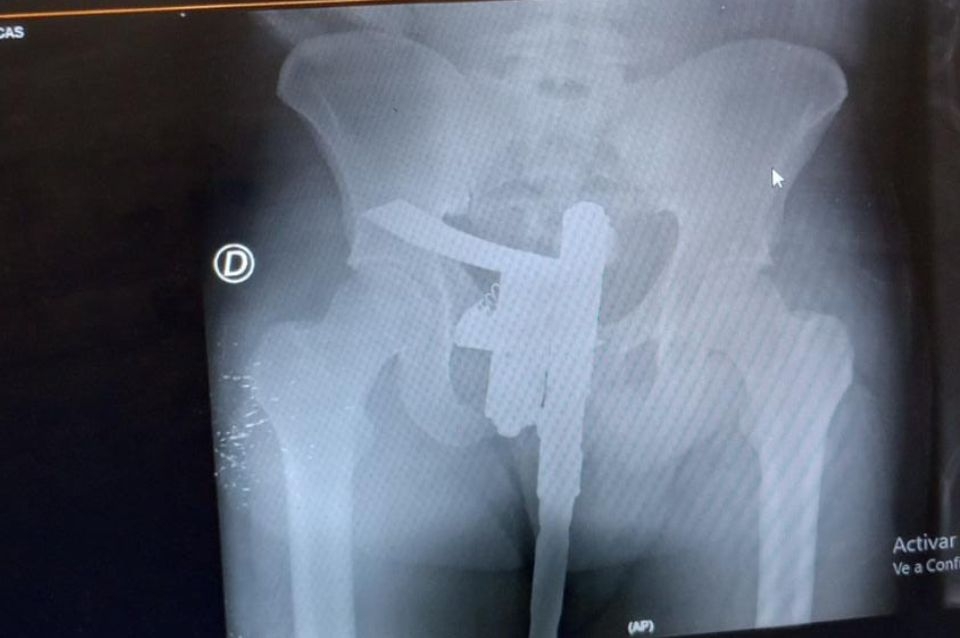

La misma fue observada a través de una radiografía y denunciada por un enfermero.

El detenido tiene 25 años, había tenido un accidente, y el arma secuestrada era de fabricación casera tipo pistola, la cual portaba entre sus ropas a la altura de los genitales.